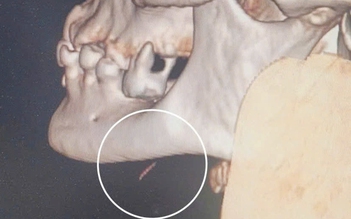

Nuốt phải xương cá, cụ bà 77 tuổi bị áp xe dưới cằm